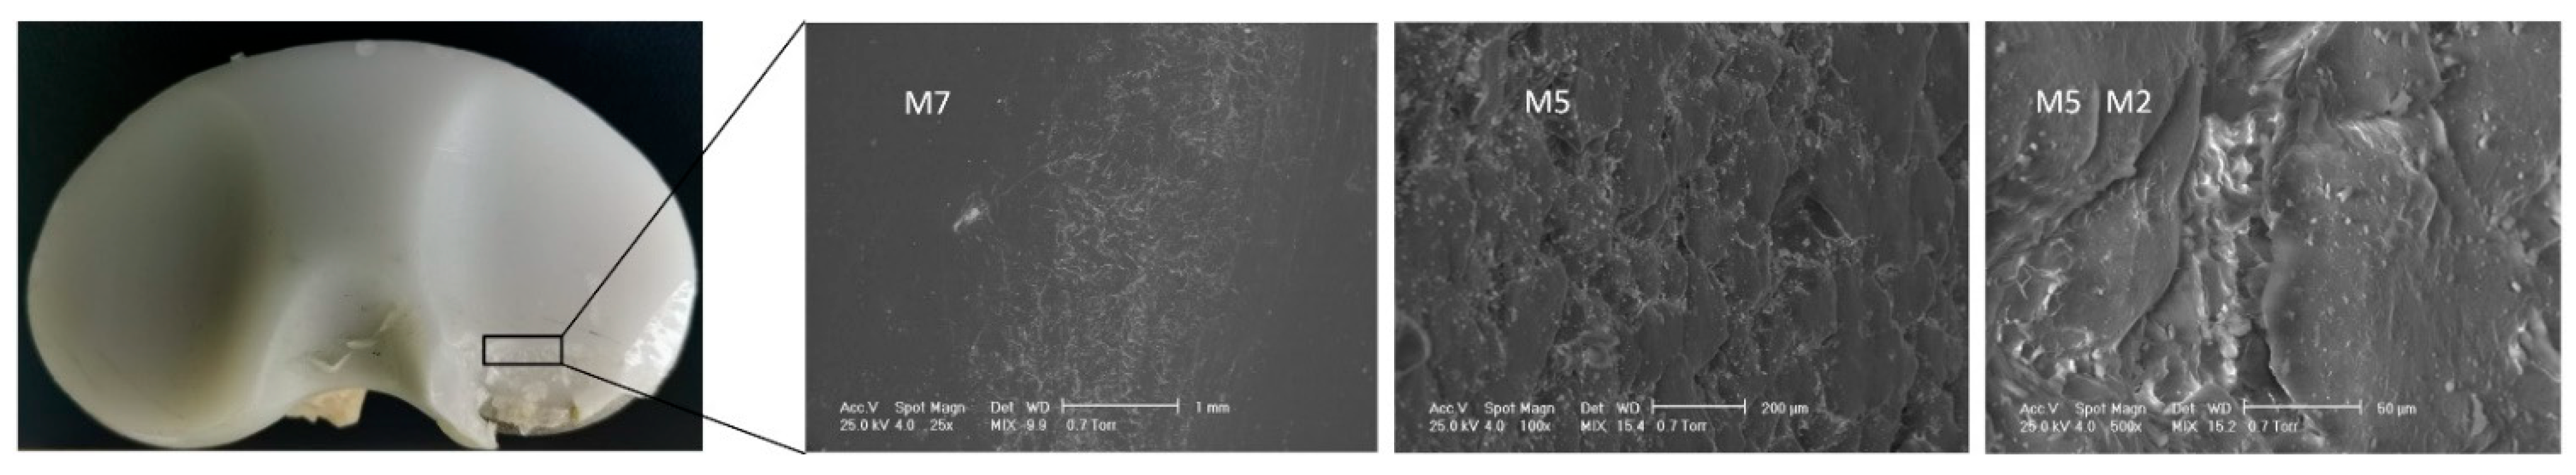

| Sample ID | Deterioration Mode | M1 | M2 | M3 | M4 | M5 | M6 | M7 |

|---|---|---|---|---|---|---|---|---|

| IT1 | Zone | - | 3, 7 | - | 6 | 0, 7, 8, 9 | - | 7 |

| Grade | 0 | 1, 1 | 0 | 1 | 1, 2, 1, 1 | 0 | 1 | |

| Hood score | 9 | |||||||

| IT4 | Zone | 2, 3 | 1, 9 | 1,9 | 2 | 2, 5, 6, 7, 9 | - | 4, 5, 6, 9 |

| Grade | 1, 1 | 1, 1 | 2, 1 | 2 | 2, 3, 3, 3, 1 | 0 | 3, 3, 3, 2 | |

| Hood score | 32 | |||||||